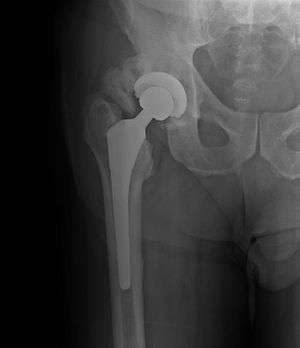

| Heterotopic ossification around the hip joint in a patient who has undergone hip arthroplasty | |

Heterotopic ossification (HO) is the process by which bone tissue forms outside of the skeleton.

Heterotopic ossification of varying severity can be caused by surgery or trauma to the hips and legs. About every third patient who has total hip arthroplasty (joint replacement) or a severe fracture of the long bones of the lower leg will develop heterotopic ossification, but is uncommonly symptomatic. Between 50% and 90% of patients who developed heterotopic ossification following a previous hip arthroplasty will develop additional heterotopic ossification.